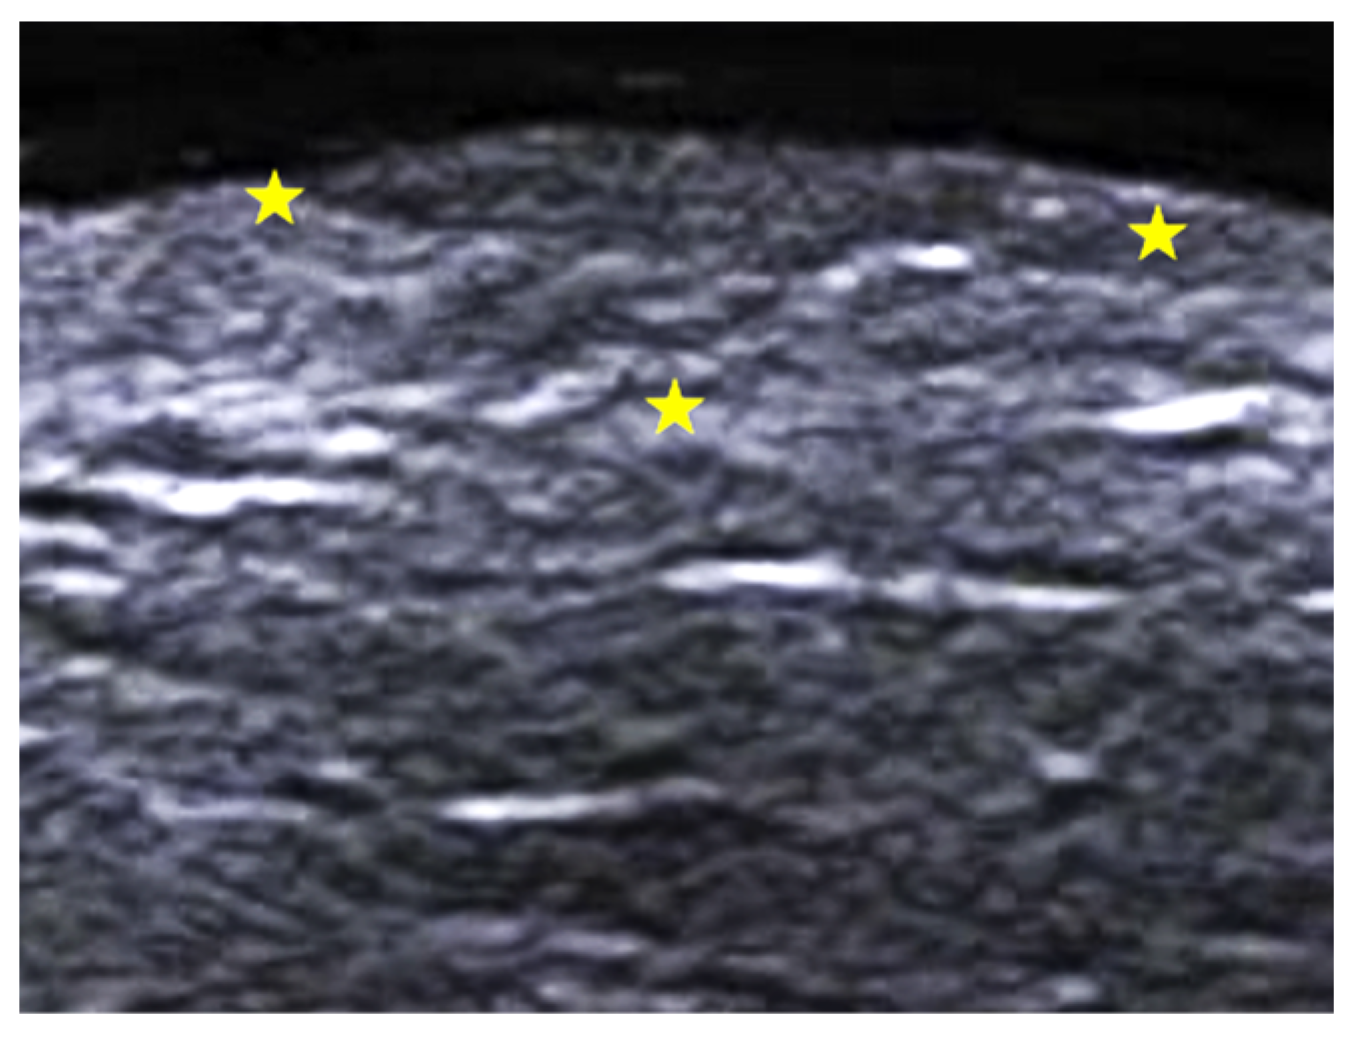

- Granieri, G.; Michelucci, A.; Manzo Margiotta, F.; Cei, B.; Vitali, S.; Romanelli, M.; Dini, V. The Role of Ultra-High-Frequency Ultrasound in Pyoderma Gangrenosum: New Insights in Pathophysiology and Diagnosis. Diagnostics 2023, 13, 2802. [Google Scholar] [CrossRef] [PubMed]